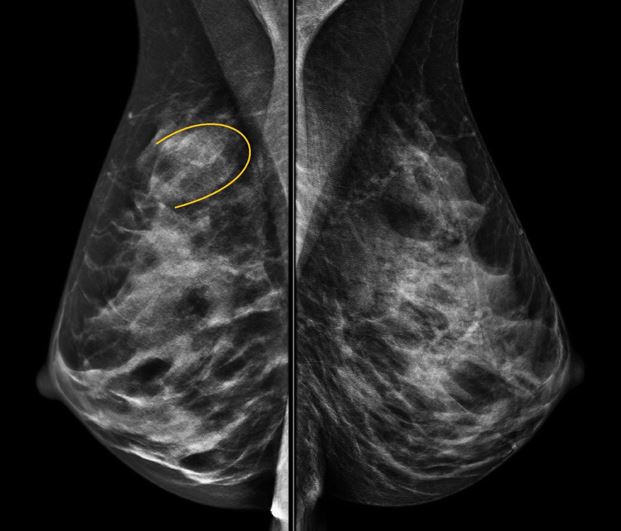

Феномен гипердиагностики в маммографии: примеры и иллюстрации

Раздел: Образы вокруг